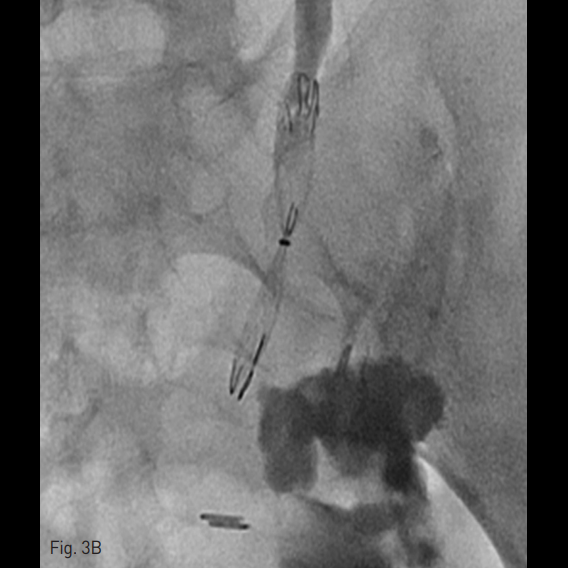

성공적으로 스텐트를 위치시킨 것이 확인된 후 (Fig. 3A) 조영제를 재주입하여 추가적인 누출이 없는 것을 확인하였다 (Fig. 3B).

Fig. 3. Percutaneous placement of the ureteral occlusion stent.

A. The ureteral occlusion stent is being deployed by pulling back the introducer sheath which has a radiopaque distal tip (arrow).